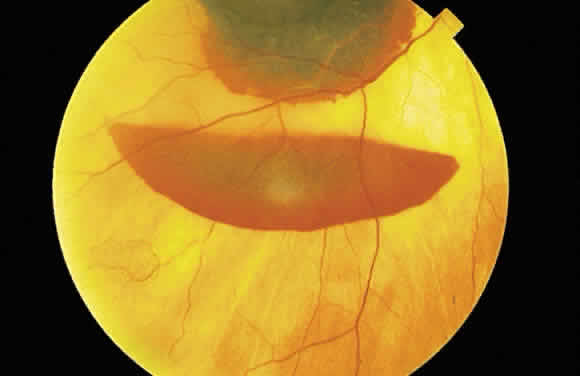

The term retinal neovascularization refers to new vessels originating within the retina that have broken through the internal limiting membrane. In early retinal neovascularization, the vessels do not invade the vitreous but lie between the internal limiting membrane and the hyaloid face (Fig. 54). These new vessels are fragile and prone to rupture and bleed. The blood may remain localized between the retina and the hyaloid (preretinal or subhyaloid hemorrhage), but with time, many of these hemorrhages break through into the vitreous itself (Fig. 55).

Fig. 55. Fundus photograph of early proliferative diabetic retinopathy. The new vessels have not invaded the vitreous, and the hemorrhage has remained between the retina and the hyaloid (preretinal/subhyaloid). Notice the vascular loops and vascular duplication.

The location of the hemorrhage also may affect is ophthalmoscopic appearance. Fresh hemorrhage between the retinal pigment epithelium and Bruch's membrane may appear brown or red-black, in contrast with the bright red color seen in fresh hemorrhages anterior to the pigment epithelium (see Fig. 13A). The location of hemorrhages within the retina also accounts for the shape of the lesion. Blood that accumulates between the nerve fiber layer and the internal limiting membrane (subinternal limiting membrane hemorrhage) (Fig. 57) assumes a shape defined by gravity, meniscus or boat-shaped, when the patient is upright (Fig. 58). The name subinternal limiting membrane hemorrhage is technically ambiguous, since a hemorrhage in the outer plexiform layer also is below (sub) the internal limiting membrane.

Fig. 58. Hemorrhage located just beneath the internal limiting membrane with the patient in the upright position. The retinal vessels are visible on the surface of the layered hemorrhage.